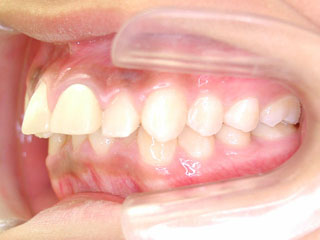

主訴:上顎前歯の突出 口が閉じにくい

診断名:叢生と伴う上顎前突

年齢:13歳

使用した主な装置名:TPB、HG、マルチブラケット装置

抜歯/非抜歯および抜歯部位:抜歯(上顎左右第一小臼歯)

治療期間:動的処置2年6か月、経過観察3年6ヶ月

費用の目安:90~140万円

リスク、副作用:抜歯によるリスク、マルチブラケット治療に伴う歯根吸収など偶発症が発生するリスクがある。

上顎前歯の前突が見られます。下の歯には中程度の叢生と口唇前突感がみられました。分析結果では、2級1類と呼ばれるタイプの不正咬合でした。上顎の左右第一小臼歯を抜歯してマルチブラケット治療を行いました。